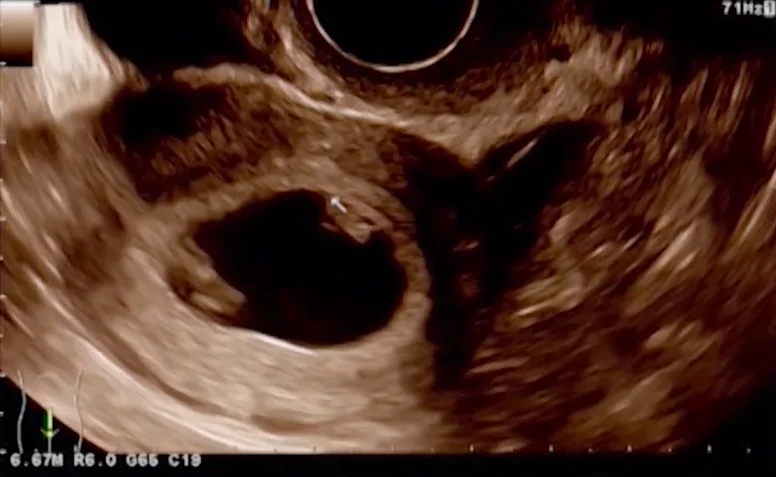

• U quái vùng cổ thai nhi (Cervical Teratoma)